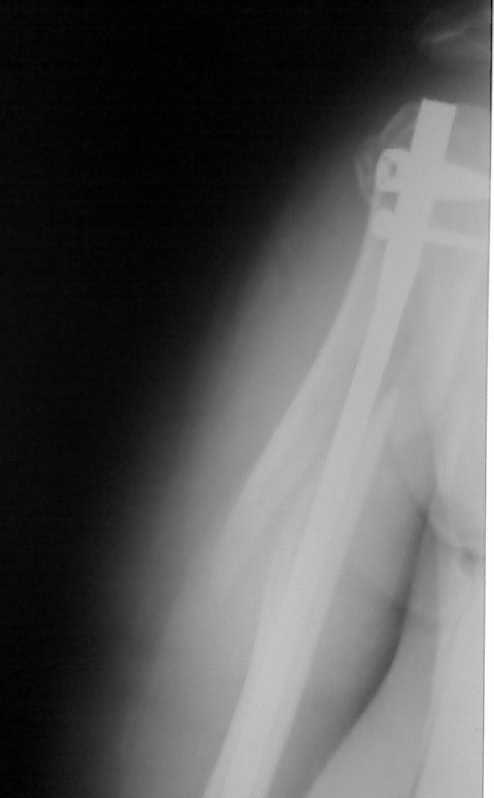

Здравствуйте уважаемые коллеги!!! Недавно стали применять в своей работе малоинвазивные методы лечения. На прошлой неделе прооперировали пожилую женщину с сопутствующим сахарным диабетом по поводу оскольчатого перелома в/3 плечевой кости штифтом PHN фирмы "Mathys". Имеется вот такое стояние костных отломков (см. рентгенограммы). Мнения коллег в отделении разделились: одни считают, что стояние отломков крайне неудовлетворительное и сращение кости при таком стоянии вряд ли возможно, другие считают, что при закрытом методе остеосинтеза и стабильной фиксации отломков результат будет благоприятный и сращение кости, даже при таком стоянии костных отломков, будет обязательно. Я придерживаюсь последнего мнения. Коллеги, каково ваше мнение? У нас это первые больные после подобных операций, поэтому большого опыта не имеем. Поделитесь своим опытом! И если это возможно, то для убедительности выложите рентгенограммы после операции и после сращения переломов с подобным стоянием отломков. Заранее СПАСИБО!!!

Приношу свои извинения по поводу рентгенорграмм! На сайт пищу первый раз. Отсылаю рентгенограмму в боковой проекции. Пациентка тучная, поэтому "пробить" ее и добится идеальных рентгенограмм не получается! Да, на снимке головка срезалась, но проблема не в ней (с головкой-то все как раз хорошо), беспокоит стояние костных отломков ниже головки... Хотя бы на основании тех рентгенограмм, которые имеются, можно получить комментарии. СПАСИБО!!!

Положение отломков диафиза приемлемое.

Высылаю рентгенограммы больной до операции и в гипсовой лонгете. Сейчас больную вообщем-то особо ничего не беспокоит, незначительная болезненность в области перелома при движениях плечом, первые два дня была отечность кисти, которая сейчас исчезла, объем движений в локтевом суставе постепенно увеличивается, отведение плеча пока небольшое. Дистальное блокирование выполнено одним винтом в передне-заднем направлении (через бицепс. Да, клинок мы конечно же заблокировали концевым колпачком. Нас тоже беспокоит возможность развития импиджмент синдрома, надеемся на то, что больная разработает движения в плечевом суставе.